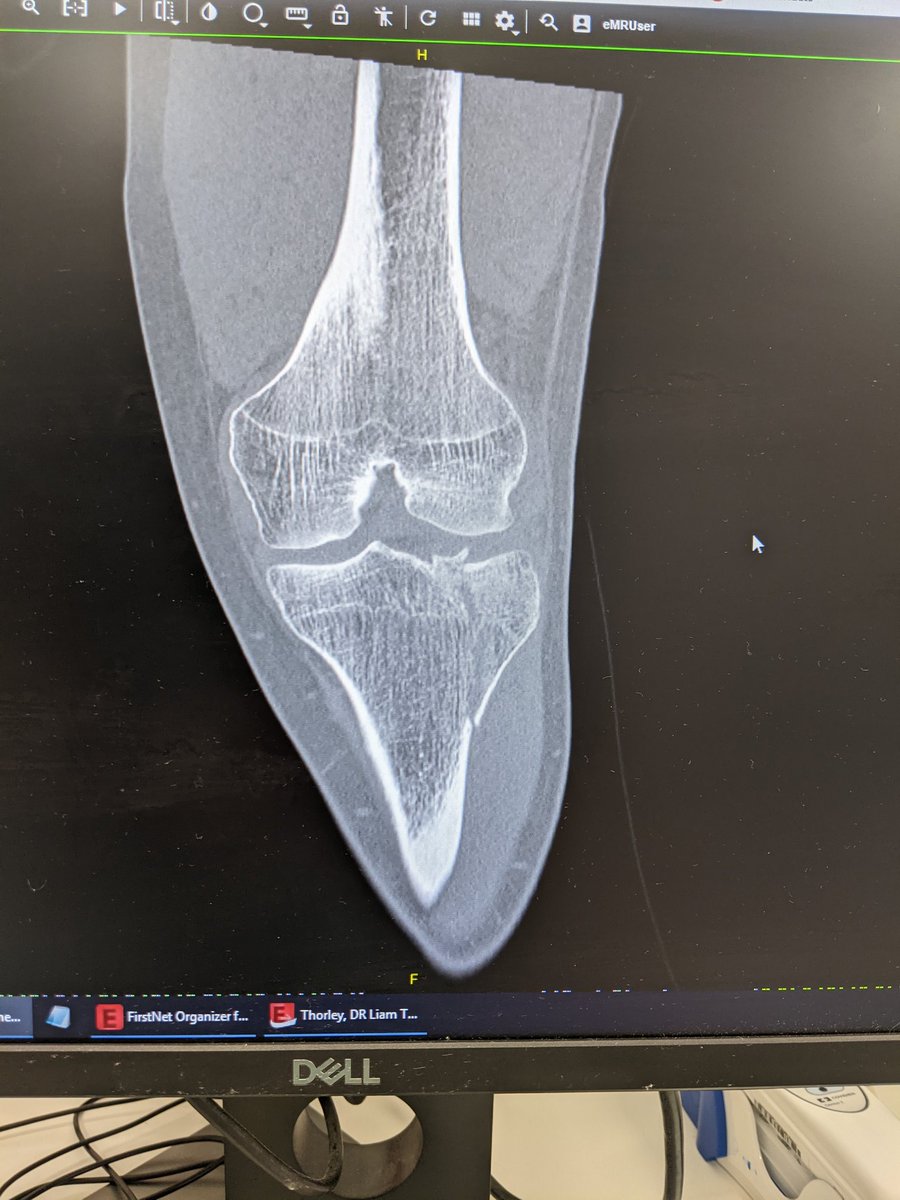

Thank you to all the fantastic nurses at Dubbo Base Hospital ED and in the surgery unit who have looked after me since getting knocked off my bike last night. ORIF done this afternoon and will start on rehab tomorrow. #InternationalNursesDay